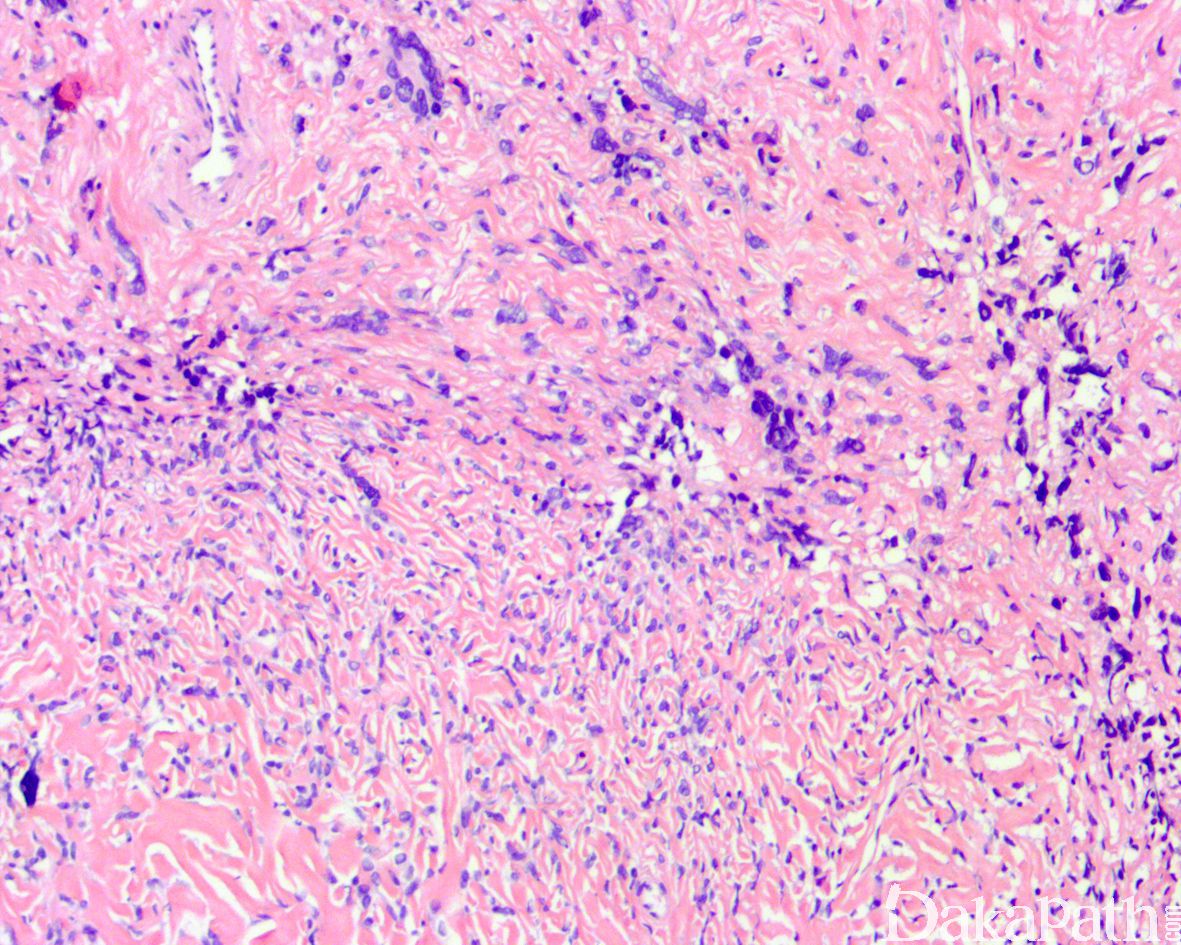

4. 镜下由交替性分布的细胞丰富区和细胞稀疏区组成;

5. 瘤细胞多呈无结构弥漫性或旋涡状生长,可见血管外皮瘤样结构(鹿角状血管),血管周硬化;

6. 瘤细胞呈梭形散在于平行的胶原中分布,大多数异形性轻微;

9. 恶性或非典型性病例:细胞密度增加,核异型性明显,核分裂 ≥4/10HPF,可见坏死,形态上类似纤维肉瘤或恶性纤维组织细胞瘤。